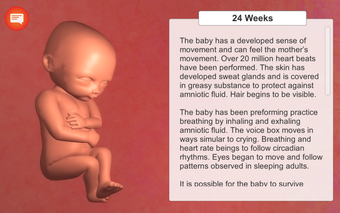

La aplicación está dividida en varias secciones, y cada sección contiene una descripción detallada y varios modelos 3D de alta calidad de las etapas clave del desarrollo del embarazo. Es muy fácil navegar por las secciones, y se puede cambiar entre ellas para ver diferentes etapas.